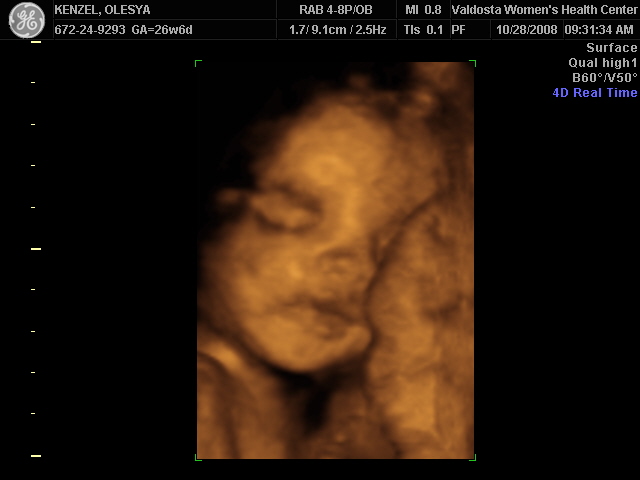

Еще одна Джианнка:

| Вложения: |

KENZEL,OLESYA_5.JPG [ 60.02 КБ | Просмотров: 1511 ]

katerina73 писал(а): Вот, пожалуй, самая лучшая фотография. Катюш, так ваш пупсик зато отлично виден, черты лица отменно видны. Те первые две вчерашние, вторые средней дочки. Со средней черты отлично видны, с этой куклой не понятно..

Катюш, какой прикольный бутузик ! Олесь, после фотки средней - точно прям похожи!